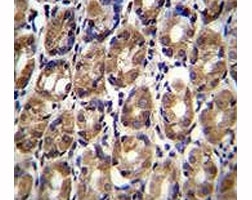

Axin-1 antibody immunohistochemistry analysis in formalin fixed and paraffin embedded human stomach tissue